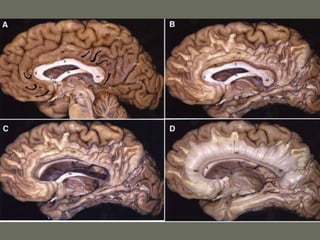

Ventricles and CSF

• CSF is produced by the choroid plexus

in the ventricles

• The circulation is from the lateral

ventricles to the third through the

Monroe- aqueduct- IV ventricle- sub

arachnoid space in skull and spine-

absorption in sss and other sinuses

through arachnoid granulations

Ventricles and CSF •CSF is produced by the choroid plexus in the ventricles • The circulation is from the lateral ventricles to the third through the Monroe- aqueduct- IV ventricle- sub arachnoid space in skull and spine- absorption in sss and other sinuses through arachnoid granulations